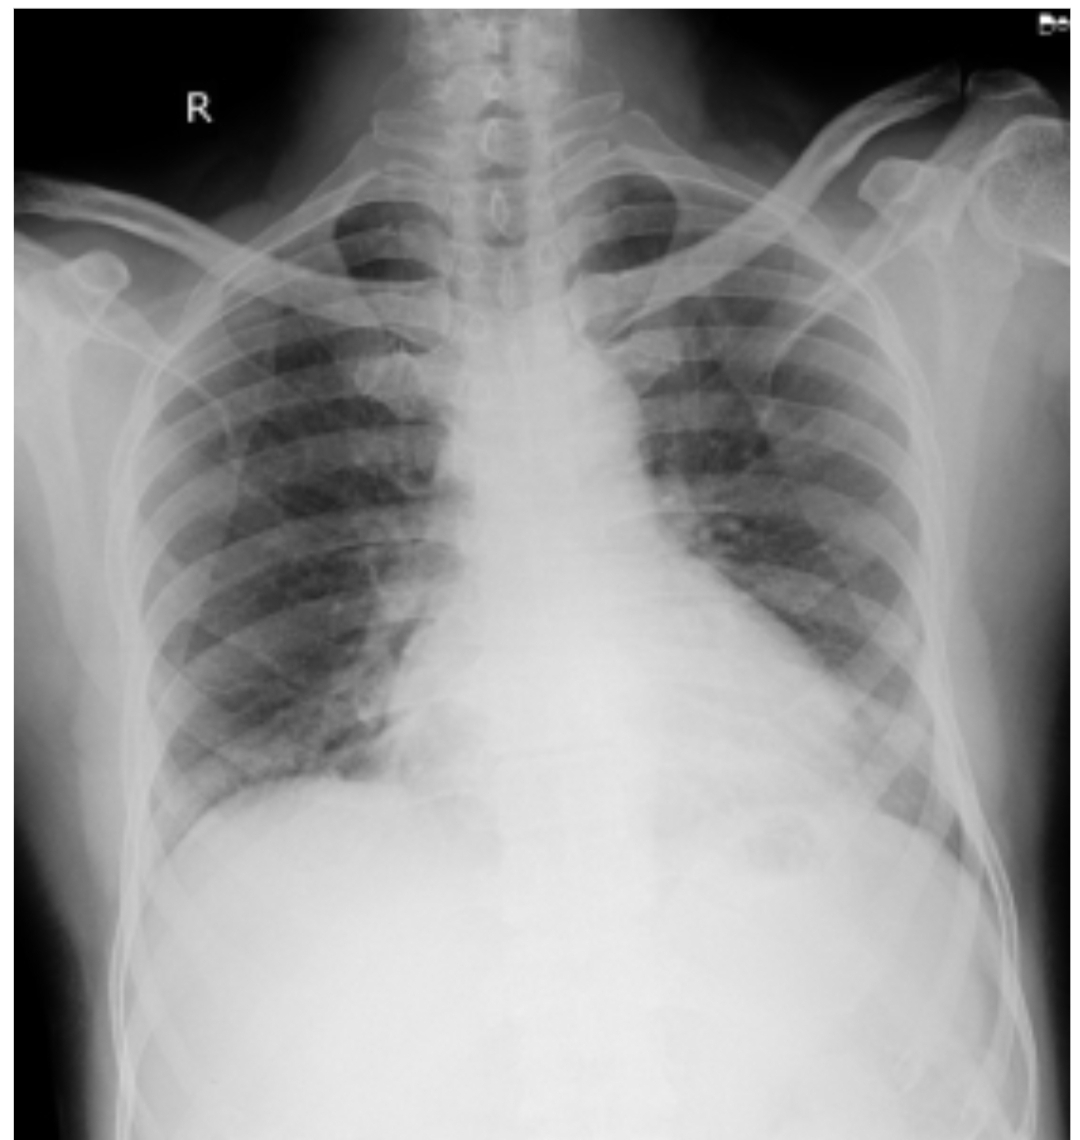

Chest x ray: